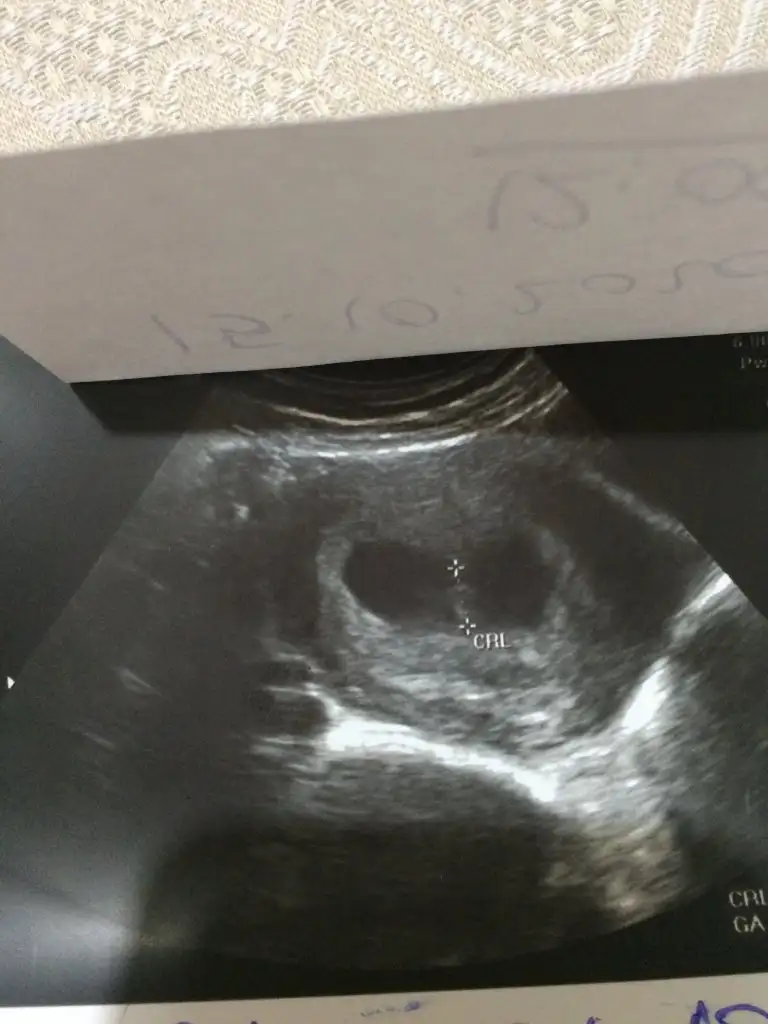

dr soylemeden siz gorun genital nub teorisi ( bebegin cinsiyeti)

Keseye göre kız 11 12 13 haftalar olmalı canım

6-7 haftalık gebelikte bebek plasentaya çok yakın konumdadır ve elinizdeki vajinal görüntüde bebek sağdaysa erkek. Bu yöntem %97 doğrudur yazıyor sitede